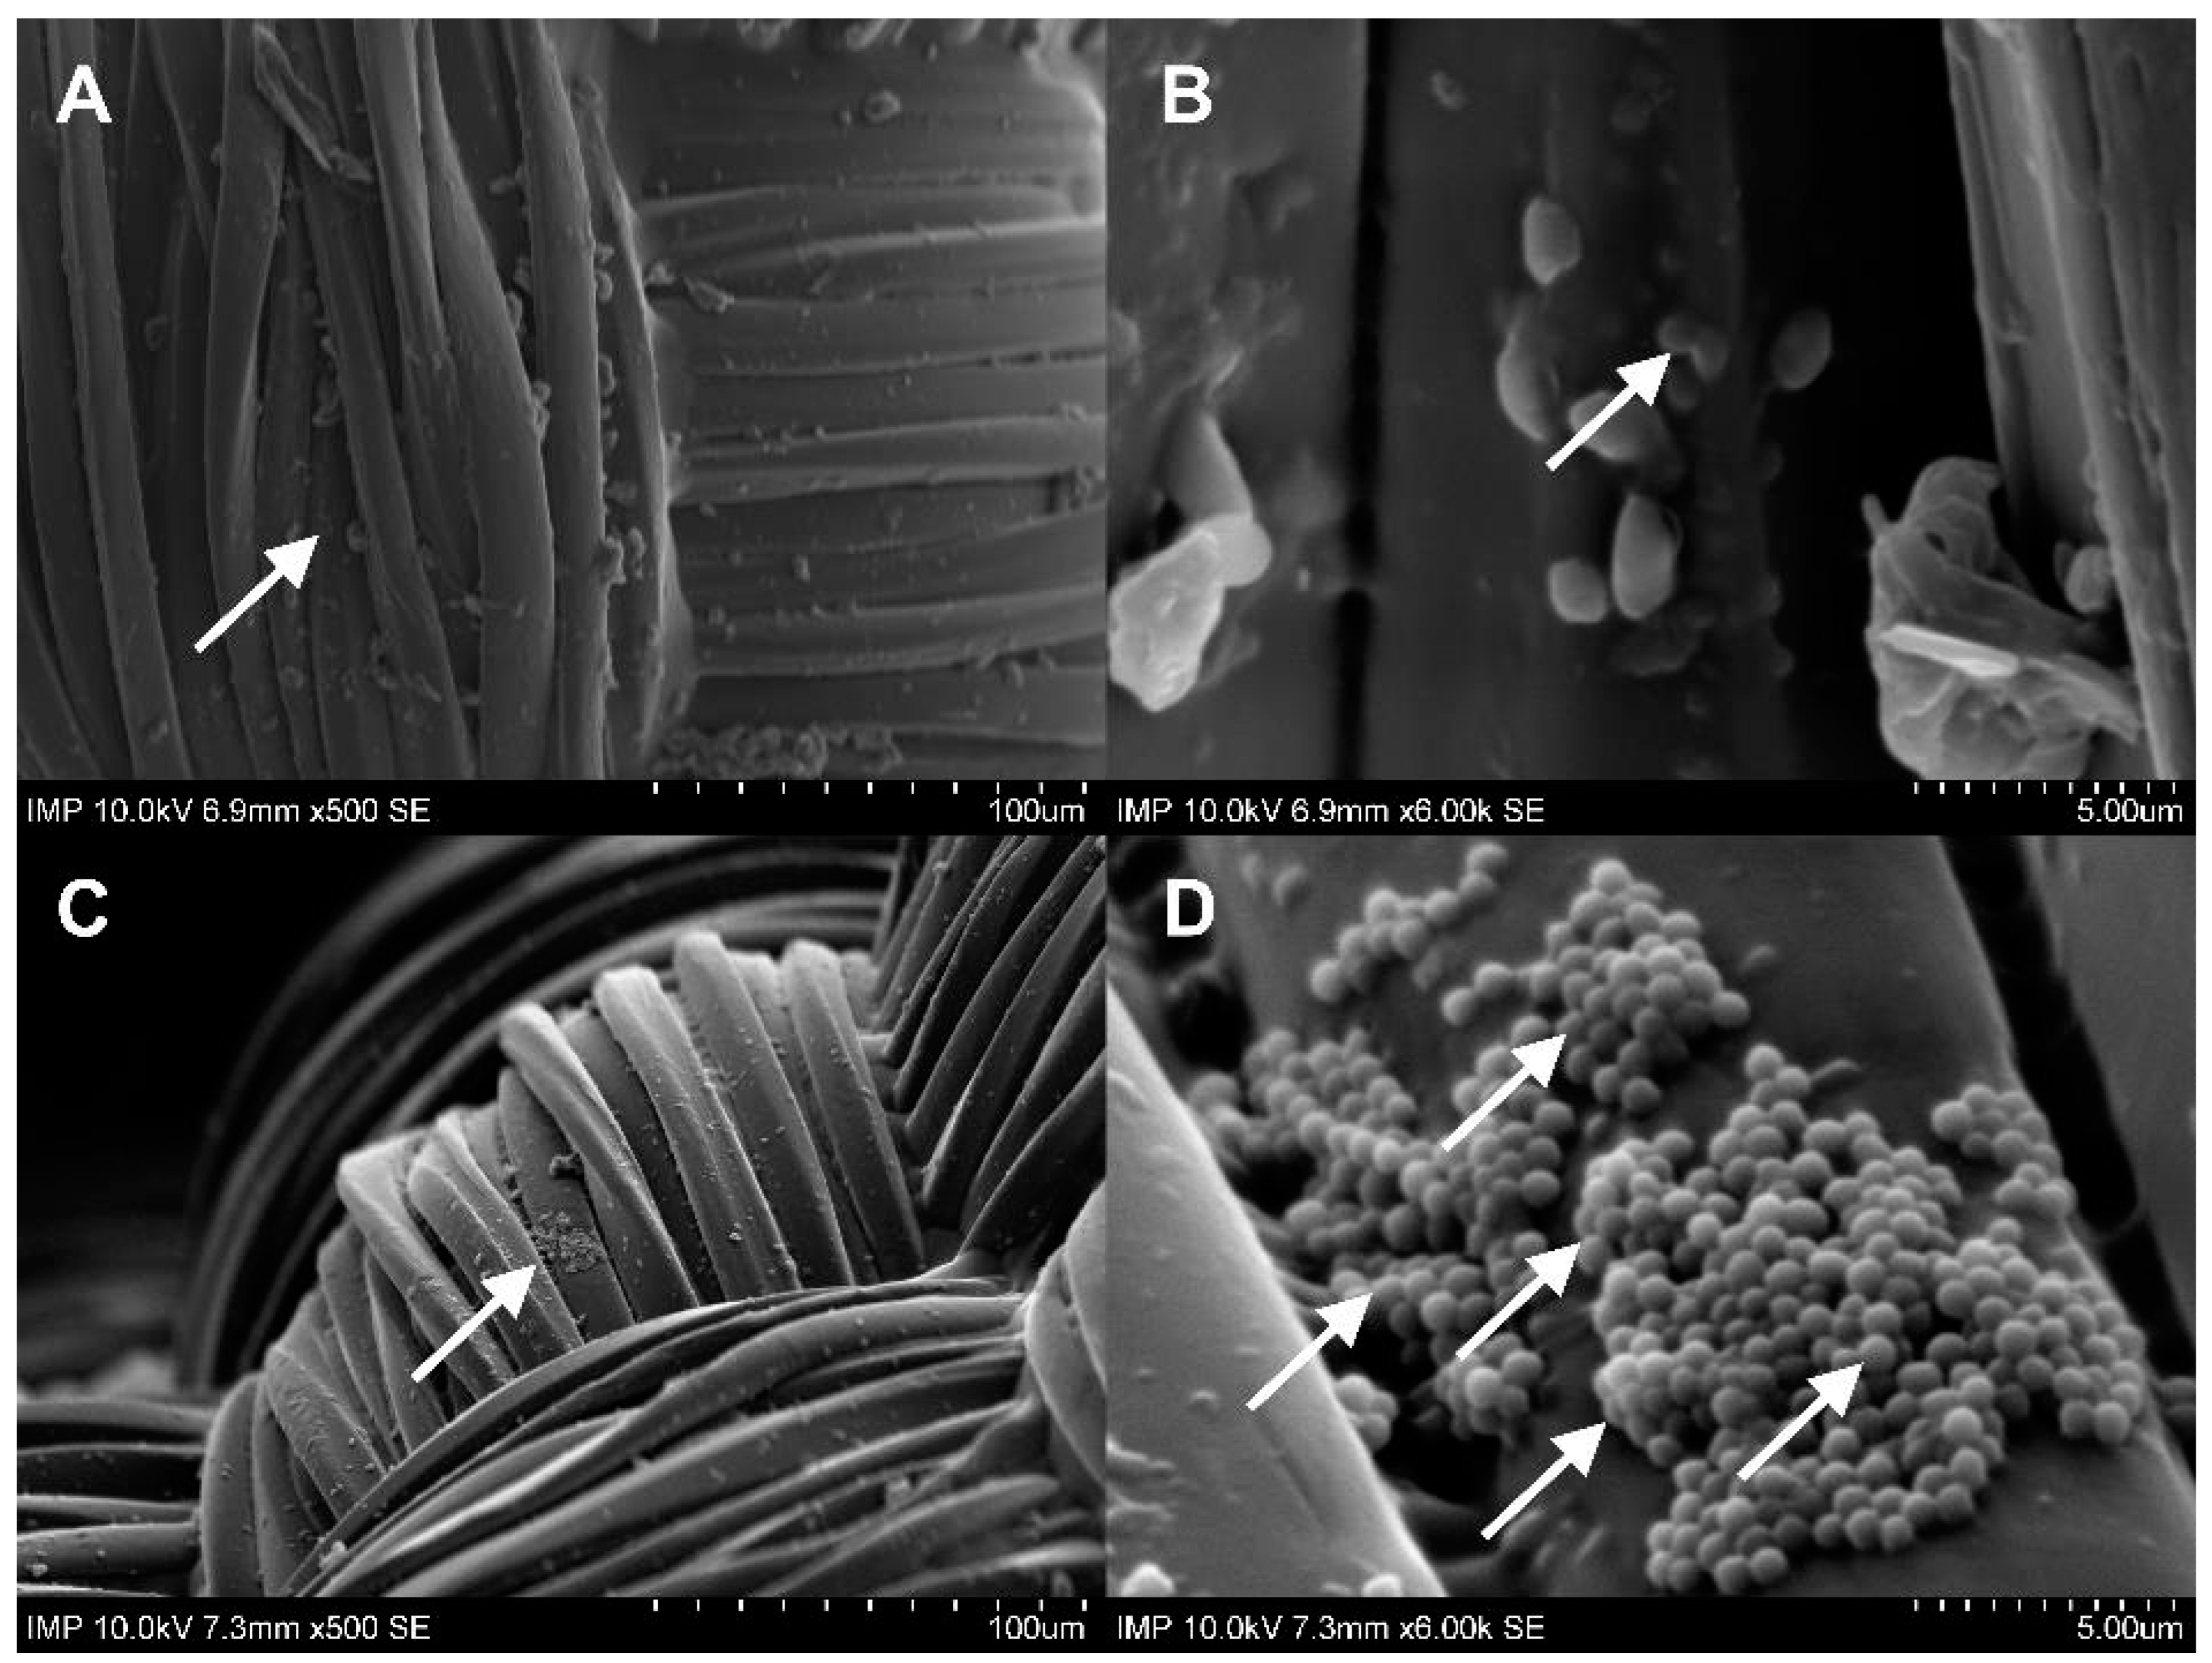

2.1. Surface Coating of the Grafts

2.3.1. Activity against Staphylococcus aureus

2.3.2. Activity against Escherichia coli

4.2.5. Scanning Electron Microscopy